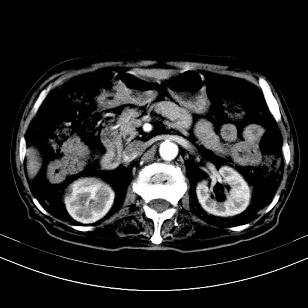

标题: CT19407:肝内还是肝外原发性肿瘤??

男,63岁,高血压病史40余年,

来源-右侧肾上腺。

考虑右侧肾上腺巨大占位;恶性?

肝内多发低密度找;转移瘤?

另:右肾结识,多发小囊肿。

考虑右肝后叶肝癌(部分外生)伴肝内多发性转移;右侧肾上腺区恶性肿瘤并肝转移待排。

考虑右侧肾上腺肿瘤并肝内多发转移。右侧肾上腺呈“八”字形,包括内侧枝及外侧枝,内侧枝受压,考虑外侧枝原发肿瘤。”

考虑肝右后叶肝癌(部分外生)伴肝内多发性转移;不排除右侧肾上腺区恶性嗜铬细胞瘤并肝转移。